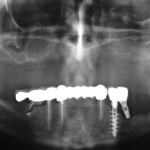

Chirurgia implantare guidata per il mascellare edentulo

L’osteointegrazione di impianti dentali endossei è universalmente accettata dai clinici di tutto il mondo sulla base di una ricerca pre-clinica e clinica significativa. Attualmente...